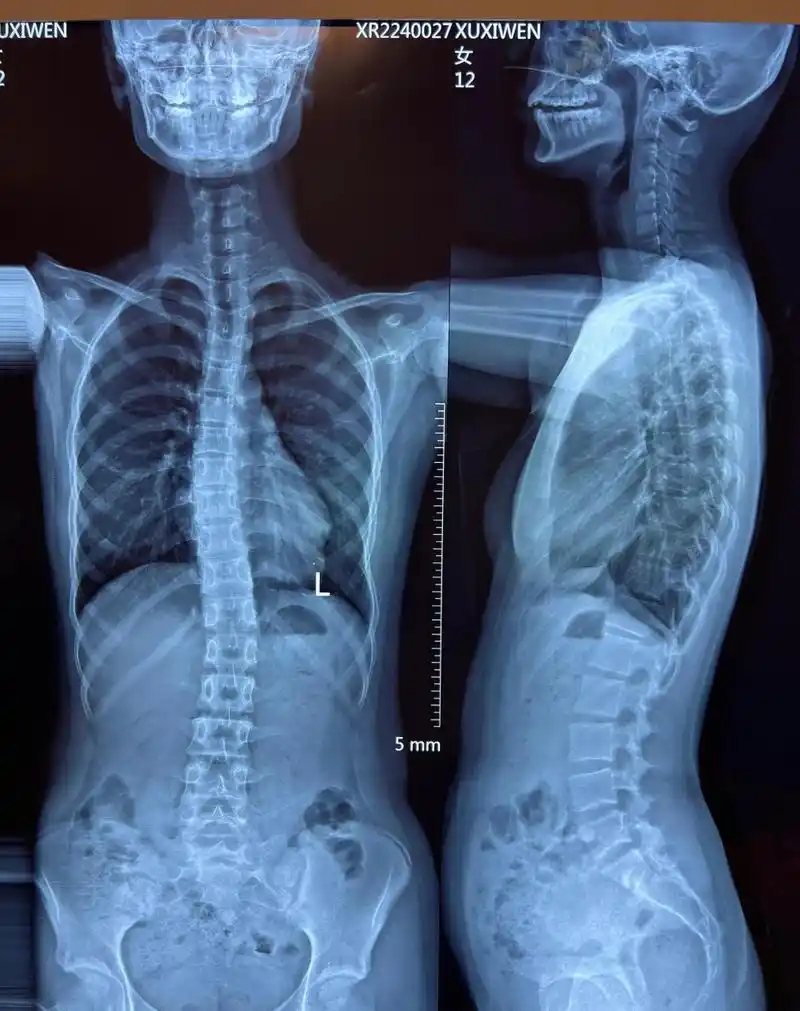

我的背后的这两个骨头为什么很凸腰挺得很直也这样为什么呢?

脊柱后凸70普陀医生帮男孩打开折叠人生